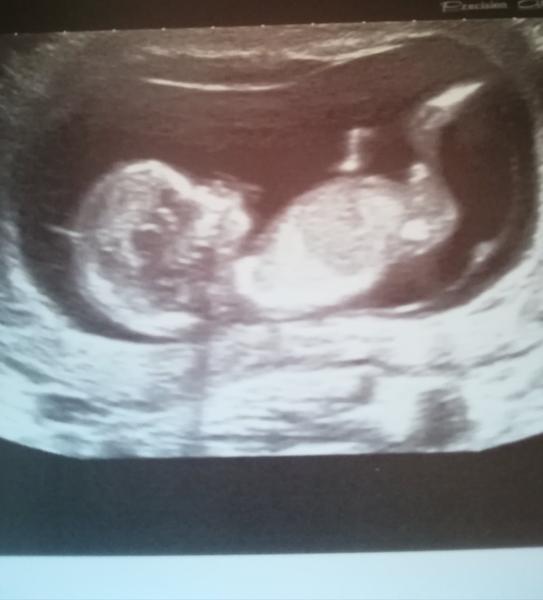

Holky tak k me fotce vyse vlozene je to kluk 😀 jako buk 😀

@krupka1 😀 vsak jsem psala tipujte :+) ja tipla kluk s je 😉

@pavlaeliska já myslim holka 😉

@ivcule123 myslim ze spis kluk 😀